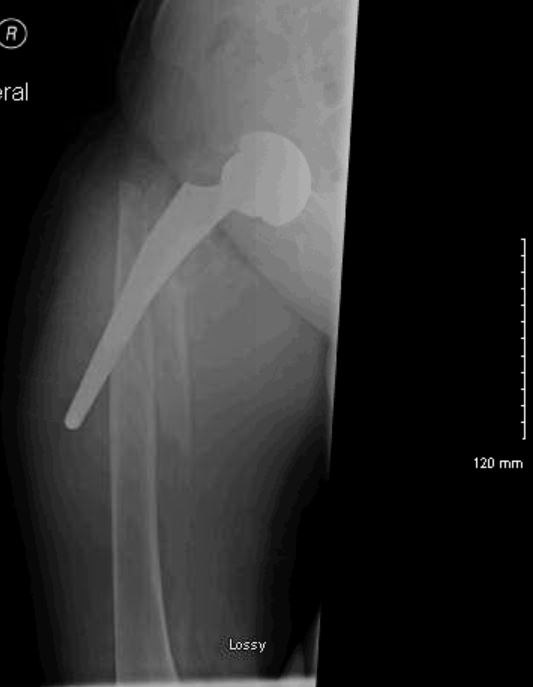

The Arcos Modular Femoral Revision System has the ability to use auxiliary implants to reattach the trochanteric fragment directly to the implant The Arcos System's three proximal and five distal geometry options provide surgeons

Zimmer Biomet's Arcos Modular Femoral Revision System meets the demands of complex hip revision surgery by offering surgeons and OR staff the ability to customize both the hip implant and its corresponding instruments Three proximal and five distal geometry options provide surgeons 117 proximal/distal combinations and multiple auxiliary. Contact a supplier or the parent company directly to get a quote or to find out a price or your closest point of sale.

Arcos Modular Femoral Revision System Hip Replacement Implant. With its broad range of femoral, acetabular, and auxiliary options, it caters to a diverse array of bone conditions, empowering surgeons to adopt a more personalised, patient-specific approach. 2,308 views February 07, 2022 Posted in HipsCenter, Zimmer Biomet Hip.